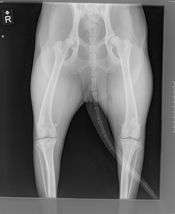

An arm radiograph, demonstrating broken ulna and radius with implanted internal fixation.

A radiograph is an X-ray image obtained by placing a part of the patient in front of an X-ray detector and then illuminating it with a short X-ray pulse. Bones contain much calcium, which due to its relatively high atomic number absorbs x-rays efficiently. This reduces the amount of X-rays reaching the detector in the shadow of the bones, making them clearly visible on the radiograph. The lungs and trapped gas also show up clearly because of lower absorption compared to tissue, while differences between tissue types are harder to see.